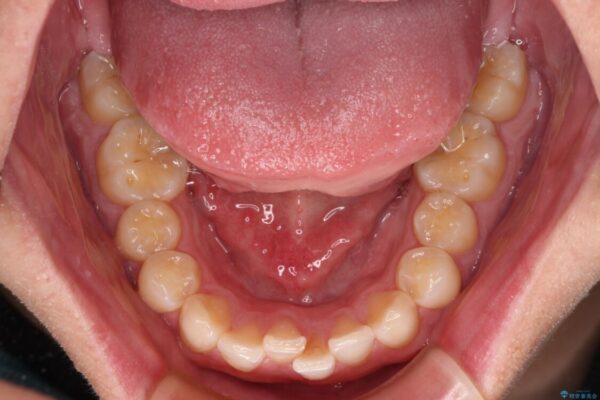

主訴:前歯のデコボコと奥歯のかみ合わせを治したい 今回ご紹介するのは、「前歯のガタガタ(叢生)」と「奥歯のかみ合わせ(シザーズバイト)」にお悩みでご来院された患者様の症例です。 患者様は、 ・歯並びをできるだけ早く改善したい ・費用を抑えた矯正治療 というご要望をお持ちでした。

・上顎左右の第二大臼歯が頬側へ転移し、シザーズバイト(scissors bite)の状態

・上顎左側第二小臼歯が90度捻転しており、噛み合わせに影響

治療前

• 前歯のガタガタ・奥歯のかみ合わせ(シザーズバイト)を改善|1年半で完了したメタルブラケット矯正 治療前画像